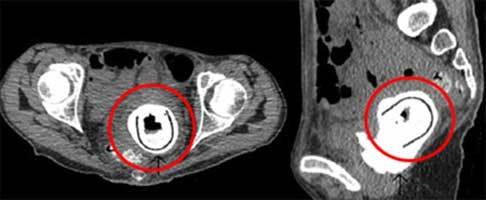

| Đồ chơi tình dục đã xâm nhập từ âm đạo vào bàng quang của bệnh nhân, rồi cư ngụ ở đó suốt 10 năm. Ảnh: Daily Mail |

Khi kiểm tra kỹ hơn, các bác sĩ kinh ngạc phát hiện một vật thể lạ xâm nhập vào bàng quang của bệnh nhân từ âm đạo. Việc phẫu thuật loại bỏ dị vật hé lộ, nó là một món đồ chơi tình dục dài 11cm.

Các bác sĩ cho biết, bệnh nhân nữ nói trên đã bị chứng rò bàng quang - âm đạo (vesicovaginal fistula) hiếm gặp, tức là phát triển một đường dẫn bất thường, cho phép nước tiểu chảy vào âm đạo. Cô cũng bị bệnh thận tắc nghẽn, trong đó một điểm tắc nghẽn ở bàng quang khiến nước tiểu chảy ngược trở lại các quả thận.